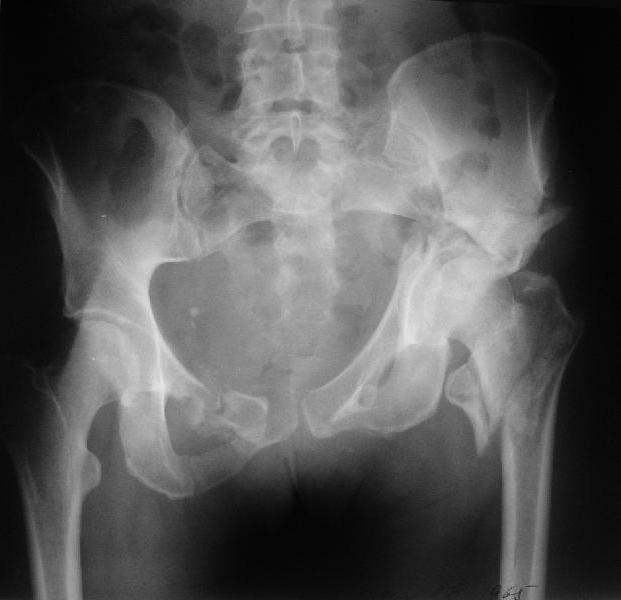

Больная 43 года (промышленный альпинист), 28.07.08 в результате падения с 5 этажа получила политравму: Перелом свода и основания черепа. Вертикально-нестабильное повреждение таза, осложнённое разрывом мочевого пузыря. Чрезвертельный перелом левого бедра. Перелом правой таранной кости, переломовывих правой кубовидной кости. Тупая травма живота, разрыв печени, ушиб почек. Забрюшинная гематома. В день травмы - лапаротомия, ушивание ран печени. Разрыв мочевого пузыря не диагностирован. Течение болезни осложнилось развитием мочевого затёка и обширной пред- и забрюшинной флегмоны, сформировался свищ мочевого пузыря. 19.8.2008 вскрытие, дренировние флегмоны, ревизия мочевого пузыря, обтурация мочевого свища (свищ закрылся в октябре), 1.10.2008 некрэктомия, пластика по Шеде-Лидскому правой кубовидной кости. По результатам КТ диагностирован рак правой почки (диагностическая находка), 8.10.2008 нефрэктомия справа. Переломы велись консервативно. Имеется вертикальное смещение левой половины таза с выраженным отведением крыла (клинически подвижности нет), несросшийся низкий двухколонный перелом левой вертлужной впадины с потерей конгруэнтности, укорочение около5 см, застарелый разрыв лонного сочленения, неправильно сросшиеся переломы обеих ветвей правой лонной кости с укорочением, патологическая подвижность лоно-седалищного фрагмента слева. Правая нижняя конечность неопорна, несмотря на то, что лежа прямую ногу поднимает, ходит на левой ноге (ортопедическая обувь) с костылями, справа тазобедренный ортез. Седалищные нервы работают.Урологи отпустили больную на 6 мес.